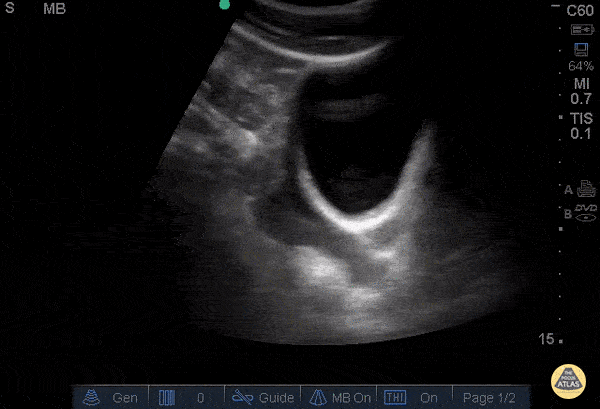

Trauma - Positive FAST - Pelvis

30 y/o pedestrian struck by car, hemodynamically unstable, tachycardic. FAST performed after primary survey revealed free fluid in all four abdominal views of the FAST exam. Free fluid seen superior and posterior to the bladder in this sagittal view. Dr. Catharine Bon - Kings County Emergency Medicine